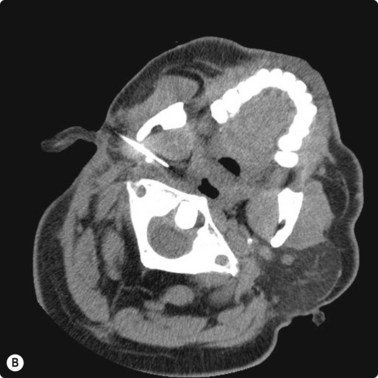

image image

Fig. 3.2 (A) Circular low dense lesion right retropharyngeal node in a patient post right parotidectomy and radiotherapy for parotid squamous cell carcinoma. (B) Coaxial fine needle aspiration biopsy technique under CT control confirmed nodal recurrence. The utility of CT biopsy techniques and fine needle aspiration biopsy helped direct this patient’s management.